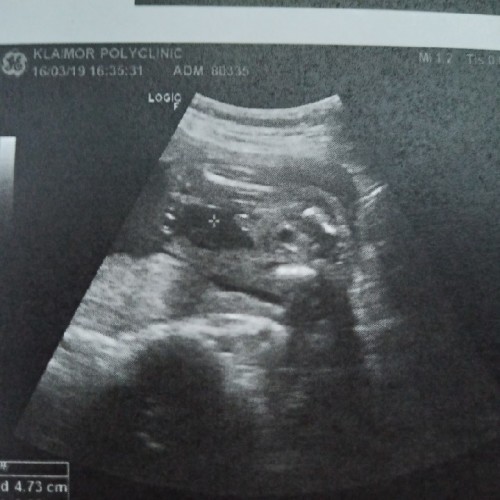

เพศทารก

แม่ๆช่วยดูหรือช่วยคอนเฟิร์มให้หน่อยค่ะว่าเพศหญิงหรือเพศชาย แม่ไม่มั่นใจ55555

แบบนี้ ผช. ค่ะ เห็นน้องท่าเดียวกัน ผญ.รึเปล่า

น่าจะหญิงนะค่ะ เห็นเป็นกีบๆ. ในภาพกี่สัปดาห์แล้วค่ะ

ถ้าให้เดาน่าจะเป็นญนะคะ ของเราหมอบอกว่าช.มีแบบนี้ค่ะ

หญิงจ้า ถ้าชายจะมีอะไรโผล่มาตรงหว่างขาแบบนี้

หญิง ไหมคะ เพราะถ้าชายจะ มีเจี้ยวโผล่ตรงกลาง

เหมือนจะหญิง ถ้าชายจะโพล่เห็นเลยกระจู๋ 😅

19คะ..เเต่เอาจิงๆเจอโด่มาแต่12วีคคะ